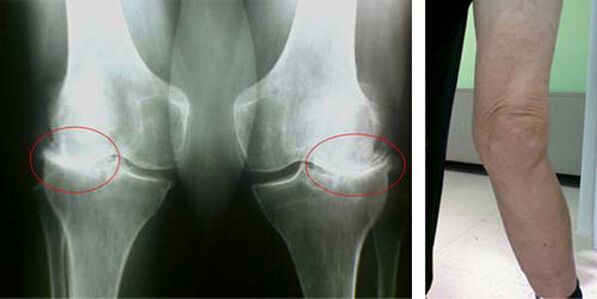

In a healthy knee joint, cartilage is a type of lining that does not allow the bones to be touched, thus eliminating the possibility of injury while walking. The diseased cartilage can not withstand this function, so in the joints appear signs of stiffness during movement, accompanied by pain. This condition becomes permanent due to internal pathological changes, when the thinning of cartilage tissue leads to thickening of the bone and creates conditions for the appearance of bone spurs - osteophytes, which provoke acute pain.

The initial stages of the appearance of a pathology such as osteoarthritis of the knee joint are not manifested visually in any way. However, after a certain time, the patient notices signs of knee deformity as well as a characteristic curvature along the axis of the lower leg (directed inwards). There is also a crack when you have to bend the leg.

The presence of pain, limited movement in the knee makes a person visit a doctor and undergo an examination. To do this, he must pass tests and do a radiograph of the diseased wrist. If these measures are not sufficient to confirm osteoarthritis of the knee, then magnetic resonance imaging is performed. Based on the data collected, the doctor selects the best treatment methods.